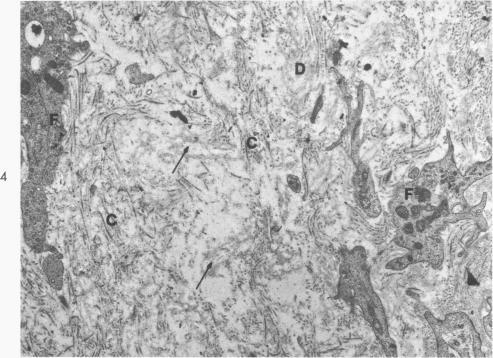

The fine structure alterations in the atrium and atrial appendage, mitral valve and papillary muscle are described in 11 matched patients with chronic rheumatic heart disease. The muscle changes consisted of loss of myofilaments and accumulation of lipid and osmiophilic dense bodies. The connective tissue stroma of the atrium and the mitral valve showed extensive deposition of collagen and elastic fibers. There were numerous foci of collagen degeneration, characterized by fraying of the collagen fibers and accumulation of homogeneous granular material at these sites. Although the muscle changes were more striking, the connective tissue alterations appear important in the evolution of the chronic disease. The extent of collagen degeneration appeared to parallel the degree of collagen formation. The muscle fiber degeneration and connective tissue alterations did not correlate with the clinical findings. At the resolution of the electron microscope, the continuing process in the rheumatic heart appears to be primarily collagen formation and degradation rather than primary degeneration of the muscle fibers. It is the balance of these processes which determine the clinical state of the patient. Acute muscle damage along with evidence of inflammation do not seem to be associated with progressive, chronic rheumatic heart disease.

在11例匹配的慢性风湿性心脏病患者中,描述了心房、心耳、二尖瓣和乳头肌的精细结构改变。肌肉变化包括肌丝丧失以及脂质和嗜锇致密小体的积聚。心房和二尖瓣的结缔组织基质显示出大量胶原纤维和弹性纤维的沉积。有许多胶原纤维变性灶,其特征为胶原纤维磨损以及在这些部位有均匀颗粒物质的积聚。虽然肌肉变化更为显著,但结缔组织改变在慢性疾病的发展过程中似乎也很重要。胶原纤维变性的程度似乎与胶原形成的程度平行。肌纤维变性和结缔组织改变与临床发现无关。在电子显微镜下观察,风湿性心脏病的持续过程似乎主要是胶原形成和降解,而非肌纤维的原发性变性。正是这些过程的平衡决定了患者的临床状态。急性肌肉损伤以及炎症证据似乎与进行性慢性风湿性心脏病无关。